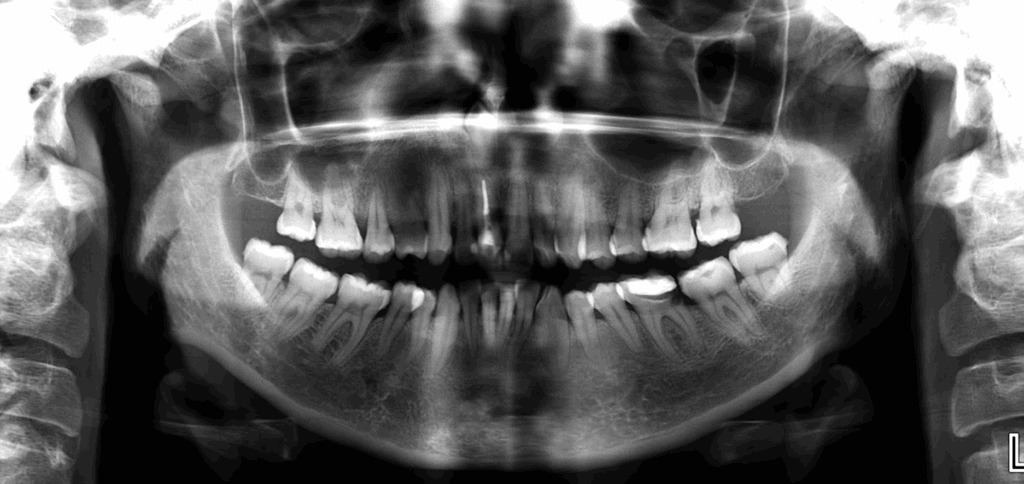

En la radiografía panorámica (Figura 1), se aprecia pieza supernumeraria invertida proyectada en zona anterior del maxilar superior.

Radiografia Panorámica